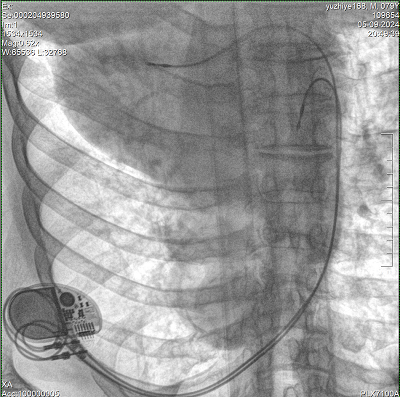

具備血管造影及數(shù)字減影(DSA)、路徑圖(Road-map)、透視、攝影等功能。 廣泛適用于介入科、血管外科、腫瘤科、消化內(nèi)科及骨科等多個(gè)臨床科室,典型應(yīng)用包括:TACE(肝腫瘤栓塞與化療灌注術(shù))、心臟起搏器置入術(shù)、四肢動(dòng)脈造影術(shù)、下肢靜脈濾器置入術(shù)、ERCP(經(jīng)內(nèi)鏡逆行胰膽管造影術(shù))等。

設(shè)備搭載自主研發(fā)的大功率高壓發(fā)生器、高熱容球管與大尺寸平板探測(cè)器,配合先進(jìn)圖像處理算法及高效冷卻循環(huán)系統(tǒng),能夠在長(zhǎng)時(shí)間手術(shù)過(guò)程中持續(xù)輸出高清圖像并保持幀率穩(wěn)定。

預(yù)留高壓注射器聯(lián)動(dòng)接口,C形臂開(kāi)始透視時(shí),高壓注射器自動(dòng)注入造影劑,提高術(shù)中造影減影效率,減少醫(yī)師手推造影劑所受到的輻射暴露劑量。